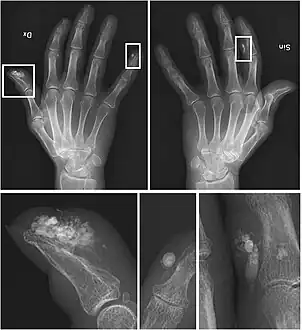

X-rays showing calcinosis in a woman with CREST syndrome -

X-ray of subtle calcifications in CREST syndrome